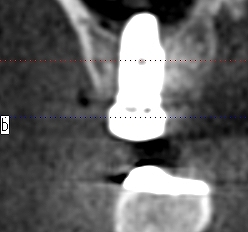

骨密度を測ります

骨の硬さを把握していきます

上顎洞までの距離はしっつかりとあるわけでもありません

この骨に上顎洞を持ち上げ5㎜幅10㎜長さのインプラントを埋入